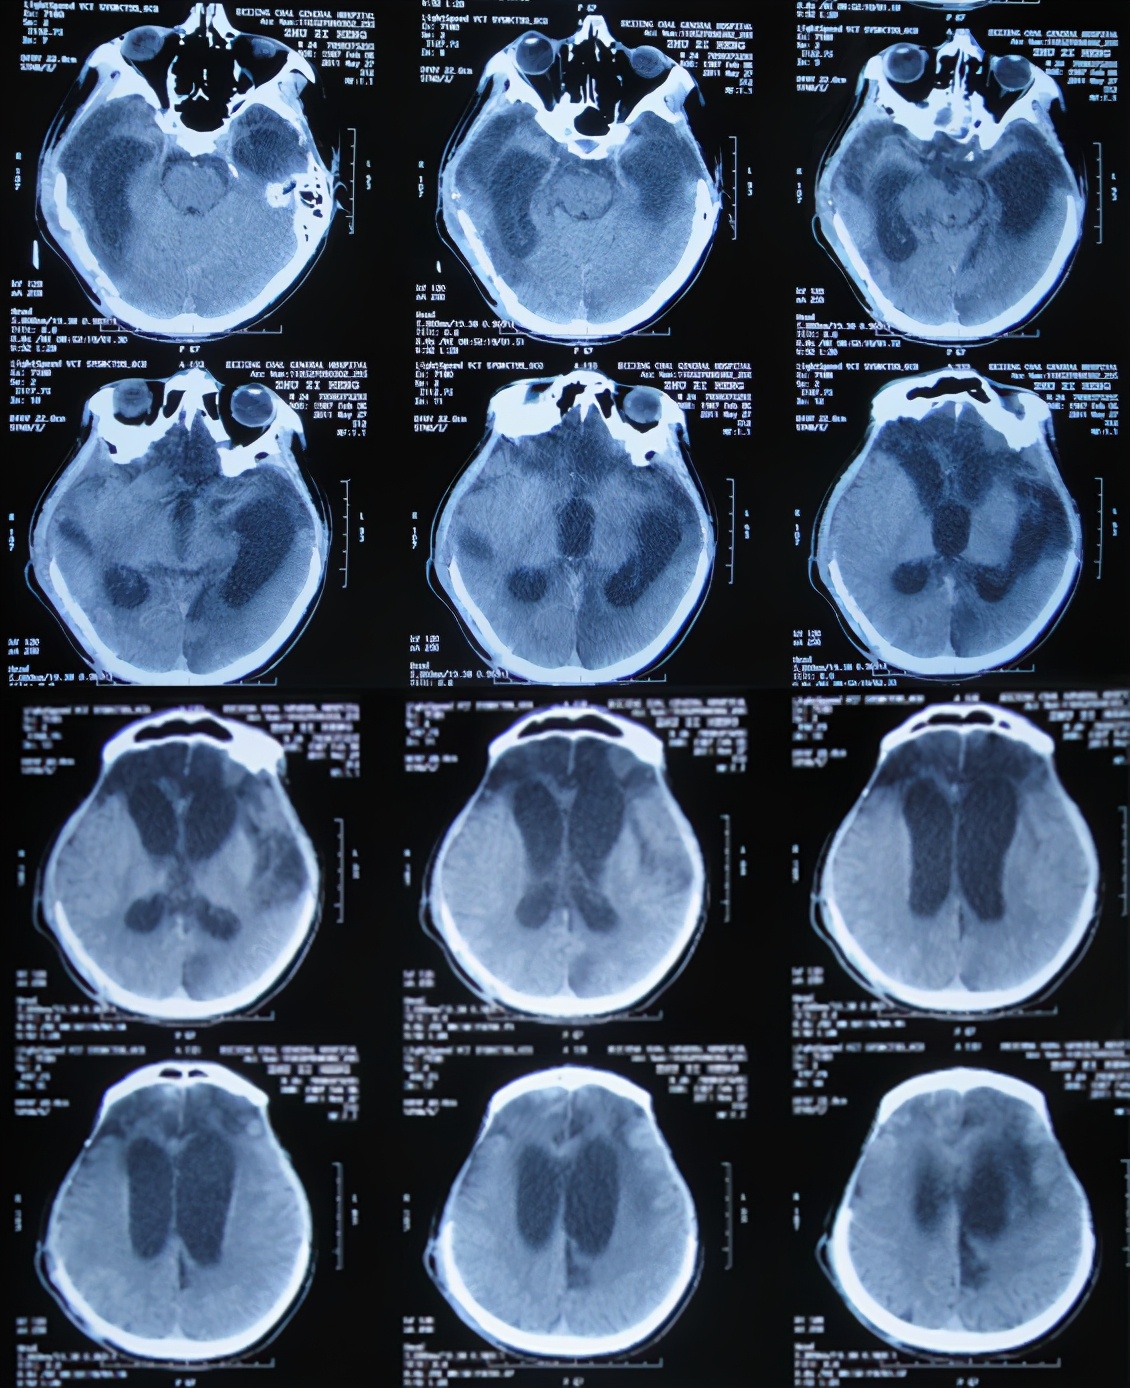

第4家医院治疗87天即开颅术后289天即2011年10月31日,因脑积水始终未得到满意治疗;期间还外请更高级的北京某三甲知名医院的专家会诊,但此专家看完头颅CT后( 图-8 )建议暂时不做腹腔分流术,因为他断定:“做了分流术之后,患者也不可能好转!”。

图-8: 2011年10月31日头颅CT

入院时:昏迷状态,刺激无发音,能自动睁眼但肢体不能遵嘱动作,不能吞咽吃饭。头部情况:双侧额颞部去骨瓣减压术后颅骨缺损,头皮手术瘢痕未见异常渗出,骨窗大小约7*8cm,头皮凹陷;头颅CT(外院2011年10月31日)提示脑外伤术后,脑积水。但右侧原手术刀口经久近1年不愈合,以往几家医院均认为除了自愈之外没有好的治疗方法。